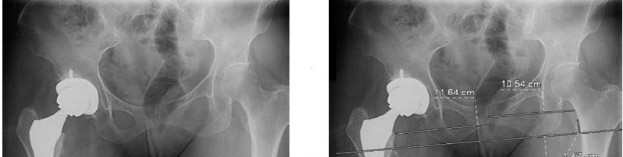

Figure 64 is the radiograph of a 77-year-old woman with a painful total hip arthroplasty (THA) who had surgery 15 years ago. Preoperative laboratory studies reveal a C-reactive protein (CRP) of 4 mg/L(reference range, 0.08-3.1 mg/L). Her serum white blood cell (WBC) count and differential values are within defined limits, and her erythrocyte sedimentation rate (ESR) is 35 mm/h (reference range, 0-20mm/h).

What is the next appropriate step in management of the patient?

Aspiration is appropriate in the setting of a failed total joint replacement when ESR and CRP are elevated,even with a normal systemic WBC count. A MRI scan of the hip is not useful in this setting. A labeled WBC scan is of no additional value when an aspiration of the hip is planned. Although multiple cultures should be obtained at the time of revision THA, preoperative aspiration is appropriate in this case. Most acetabular revisions can be accomplished with a cementless hemispherical component.